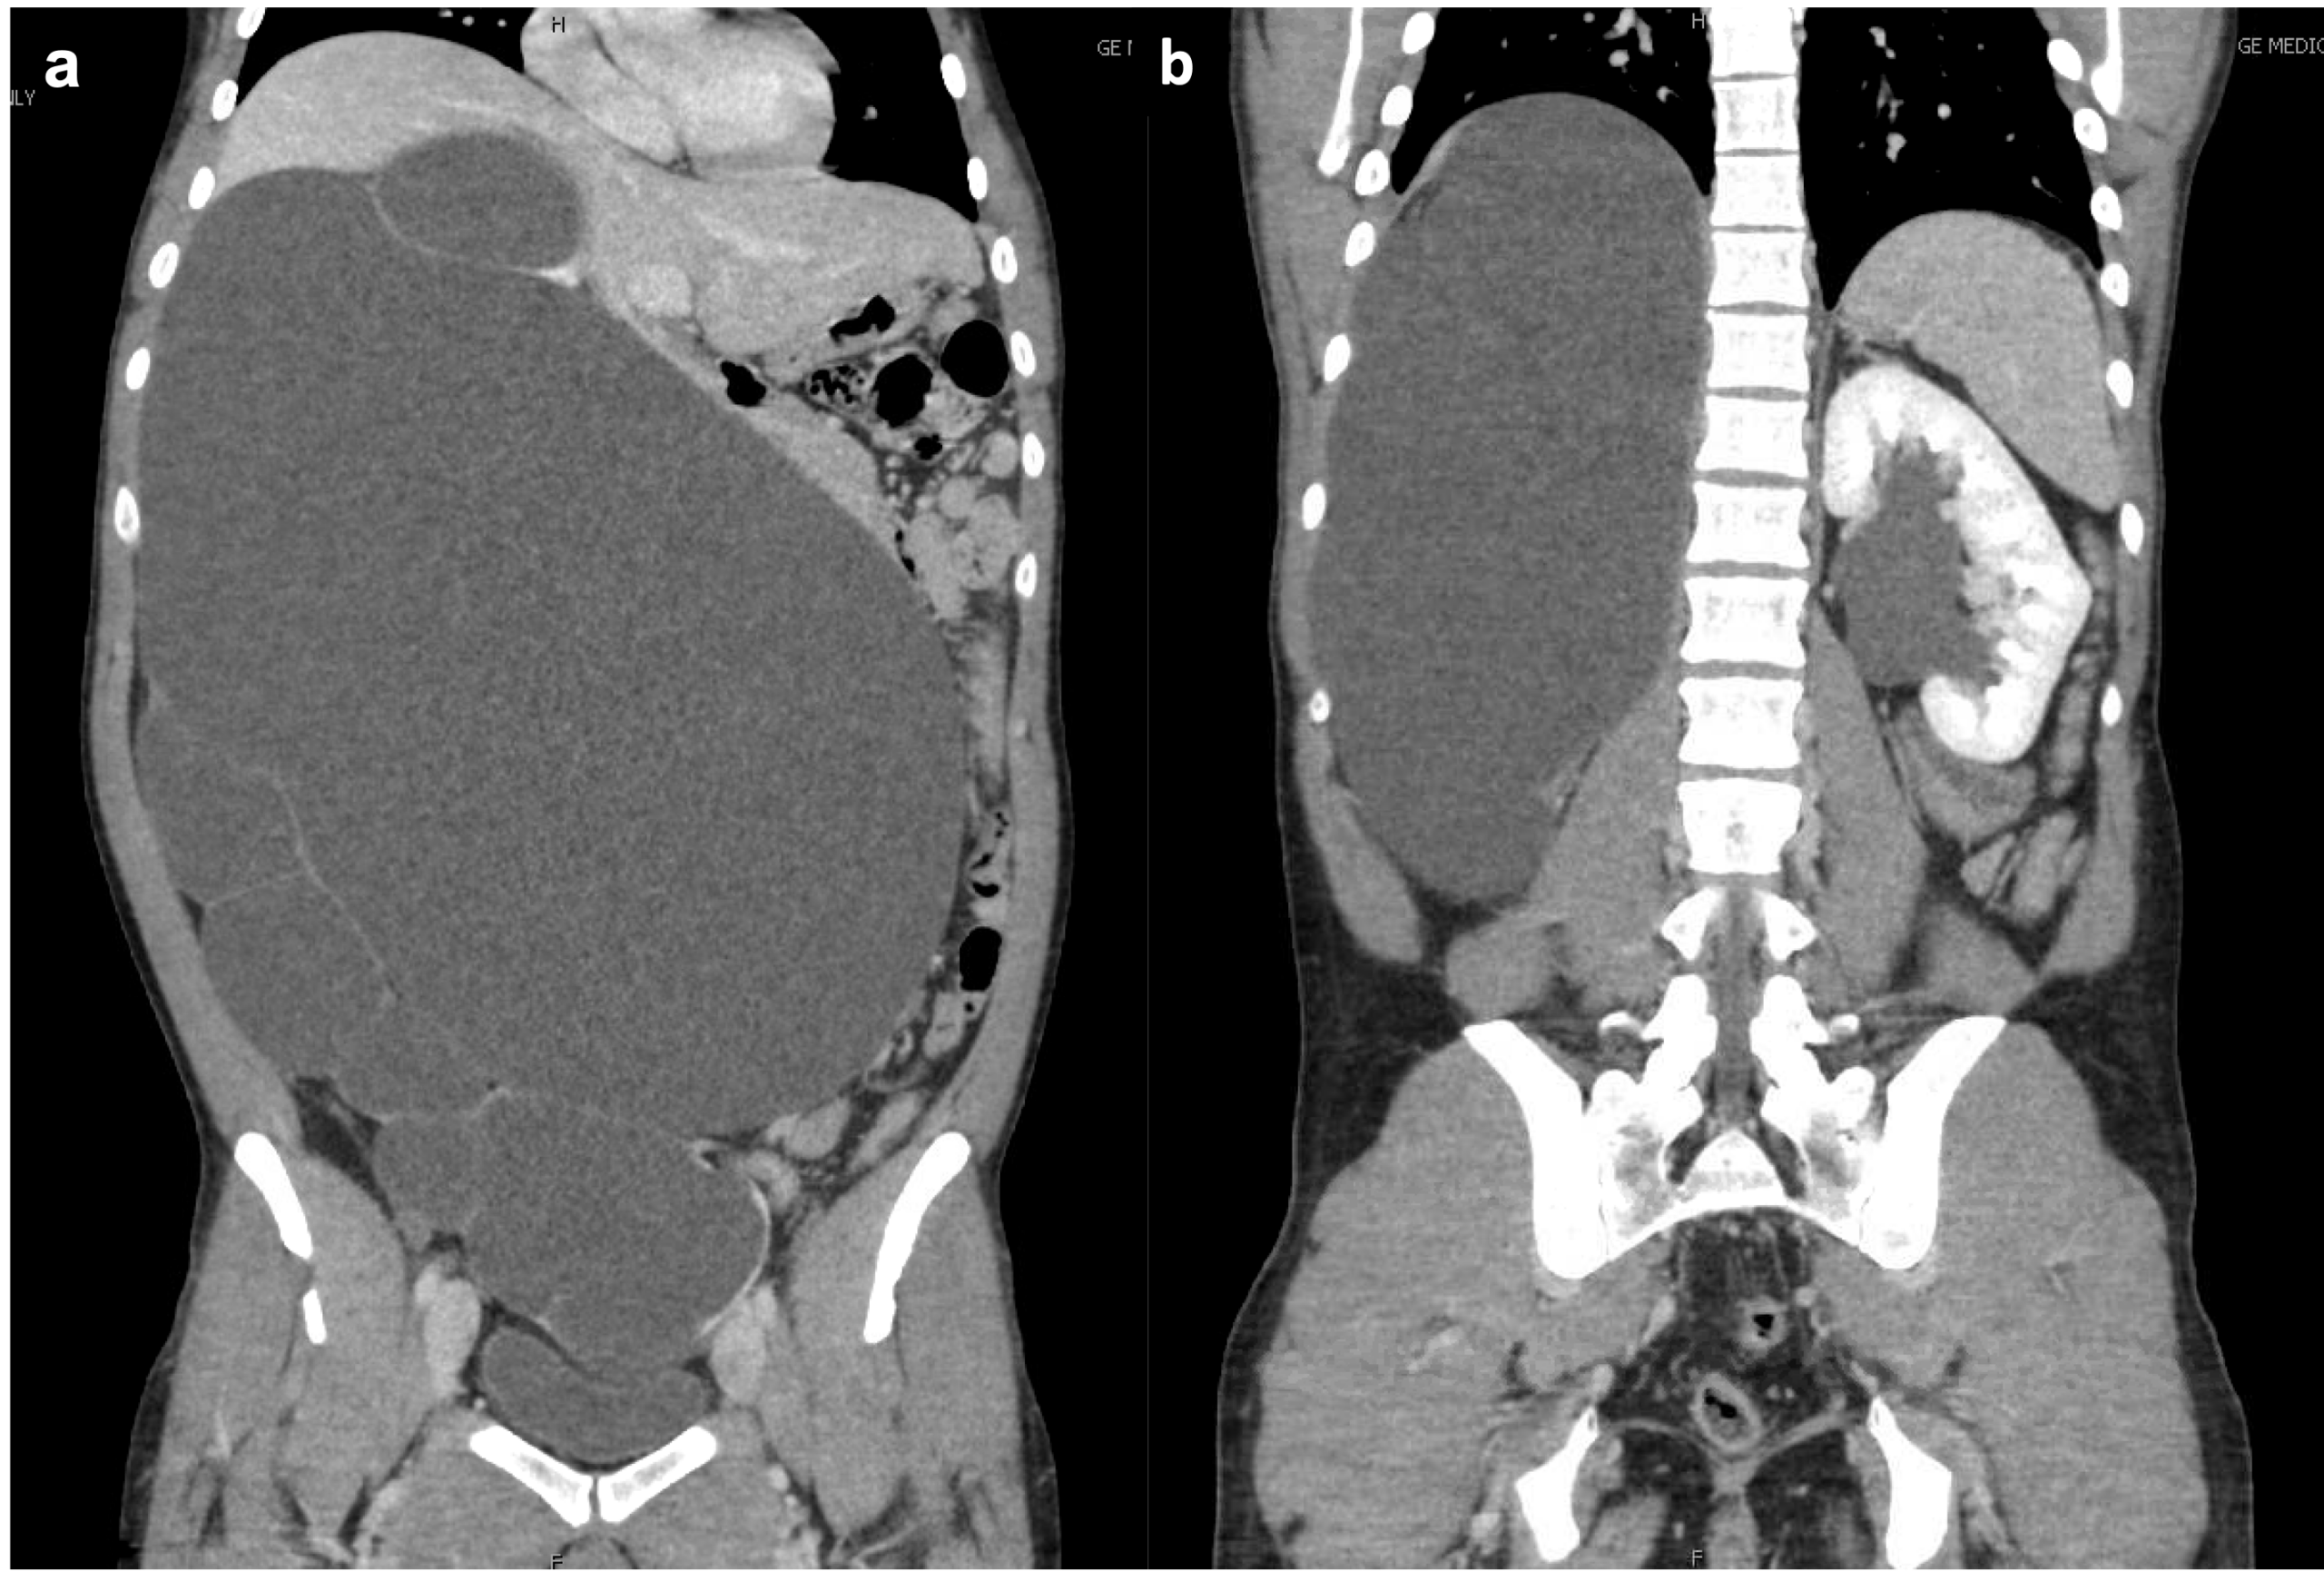

A healthy male in his early 30s had an incidental finding on abdominal sonography of a large, fluid-filled mass occupying the majority of his abdomen. Subsequent CT imaging showed massive right hydronephrosis with loss of renal parenchyma and mass effect on the intra-abdominal contents (Figure 1a). Mild left (contralateral) hydronephrosis was also noted (Figure 1b). He was subsequently referred to our institution for management.

At the conclusion of the procedure, the patient was repositioned and a retrograde pyelogram performed on the contralateral side. This demonstrated a left UPJ obstruction (Figure 2).